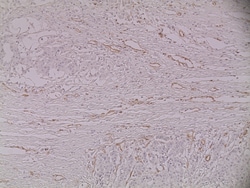

MA5-13188 targets CD31 in ICC/IF, FACS, WB and IHC (P) applications and shows reactivity with Human samples. The MA5-13188 immunogen is membrane preparation of a spleen from a patient with hairy cell leukemia.

| Applications | Flow Cytometry, Immunohistochemistry (Paraffin), Western Blot, Immunocytochemistry |